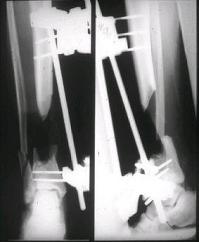

костей голени в В/3 для замешение дефекта костей. #7;#8. Постепенно

исправлена ось и возмещен дефект. В результате восстановление тыльной

флекции стопы и функции конечности. #9;#10;#11